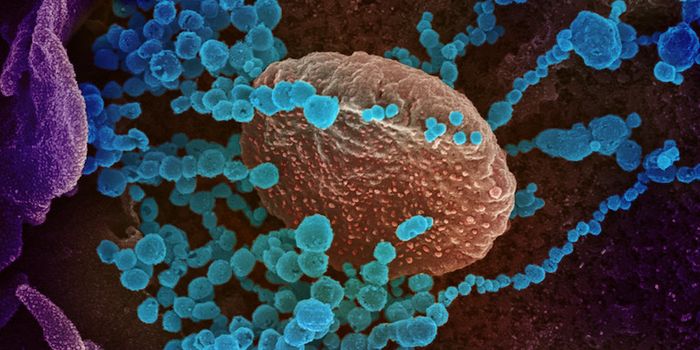

AUG 19, 2020Cell & Molecular BiologyAs the pandemic virus, SARS-CoV-2 continues to cause tens of thousands of new cases of COVID-19 every day in the United ...

APR 27, 2020MicrobiologyThe pandemic virus that causes COVID-19 has now infected nearly 3 million people, and killed over 200,000.

MAY 10, 2021MicrobiologyThe pandemic virus SARS-CoV-2 has changed the world in devastating ways, taking hundreds of thousands of lives & new var ...